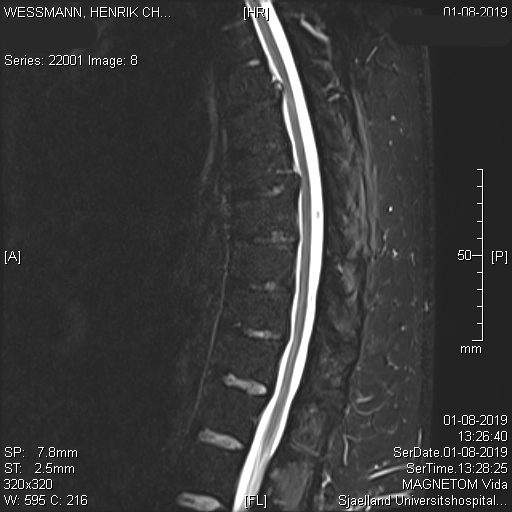

Jeg fik den store tur så de har også taget billeder af min rygmarv:

Jeg fik at vide at rygmarven skal være hvid…min har en lang sort stribe.

Hvis man ved mere om hjernen og centralnervesystemet end jeg gør kan man sikkert sige hvilke plaques, der giver mig de forskellige symptomer. Men jeg forestiller mig at den sorte stribe i rygmarven er det, som giver mig problemer specielt i mit venstre ben.

Den store plaque i hjernen er, forestiller jeg mig, den som giver mig kognitive vanskeligheder.